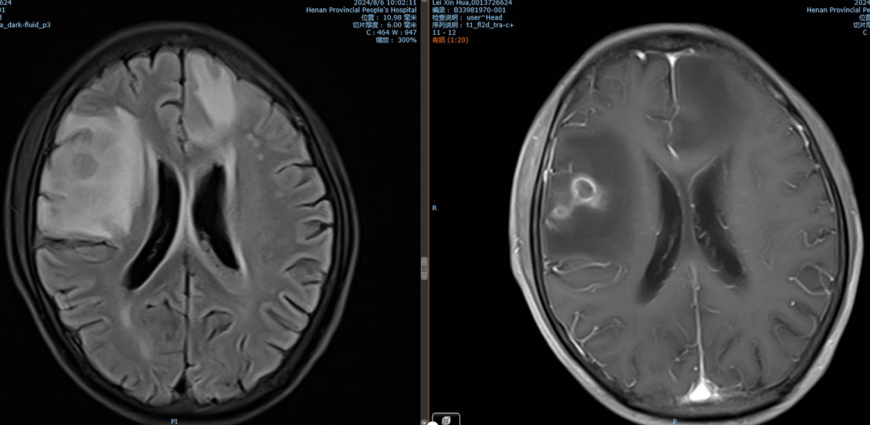

• 腹部增强CT(2023年9月17日):食管下段至贲门区域存在占位性病变,胃周可见多发肿大淋巴结(图1)。

图片1.png图1. 腹部增强CT(2023年9月17日)